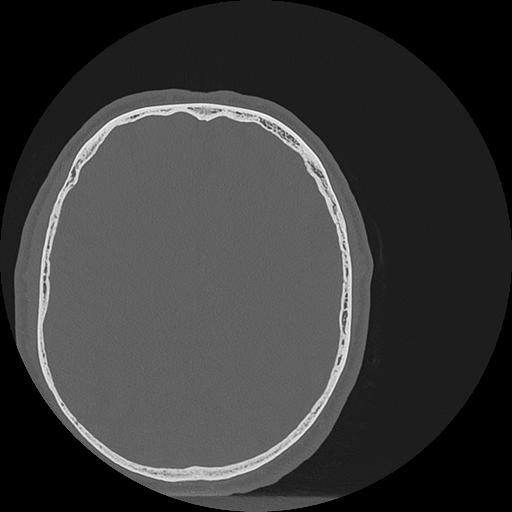

7 HUESO,,Vol,0.5,HUESO,,